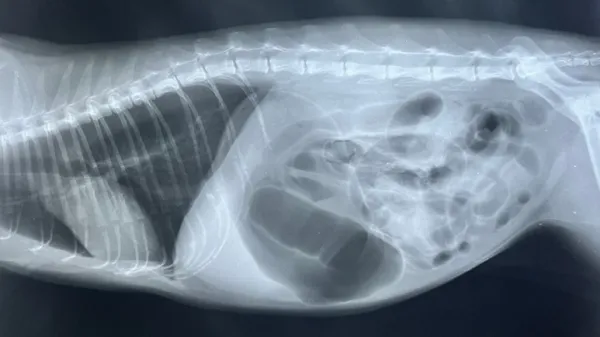

Small dogs who are past their prime may also be susceptible to collapsing trachea, which is a common condition that can bring about choking in your pet. More specifically, the C-shaped windpipe connecting their nose and mouth with the lungs is made up of cartilage.

Perhaps it's related to old age, but this area can become "floppy," and the harder the animal works to breathe in, the flatter it becomes, somewhat like a straw when you're enjoying a thick shake. Unfortunately, there's no cure for the condition as yet, but if your vet has told you your dog has this disorder, there are precautions you can take to lessen the impact.